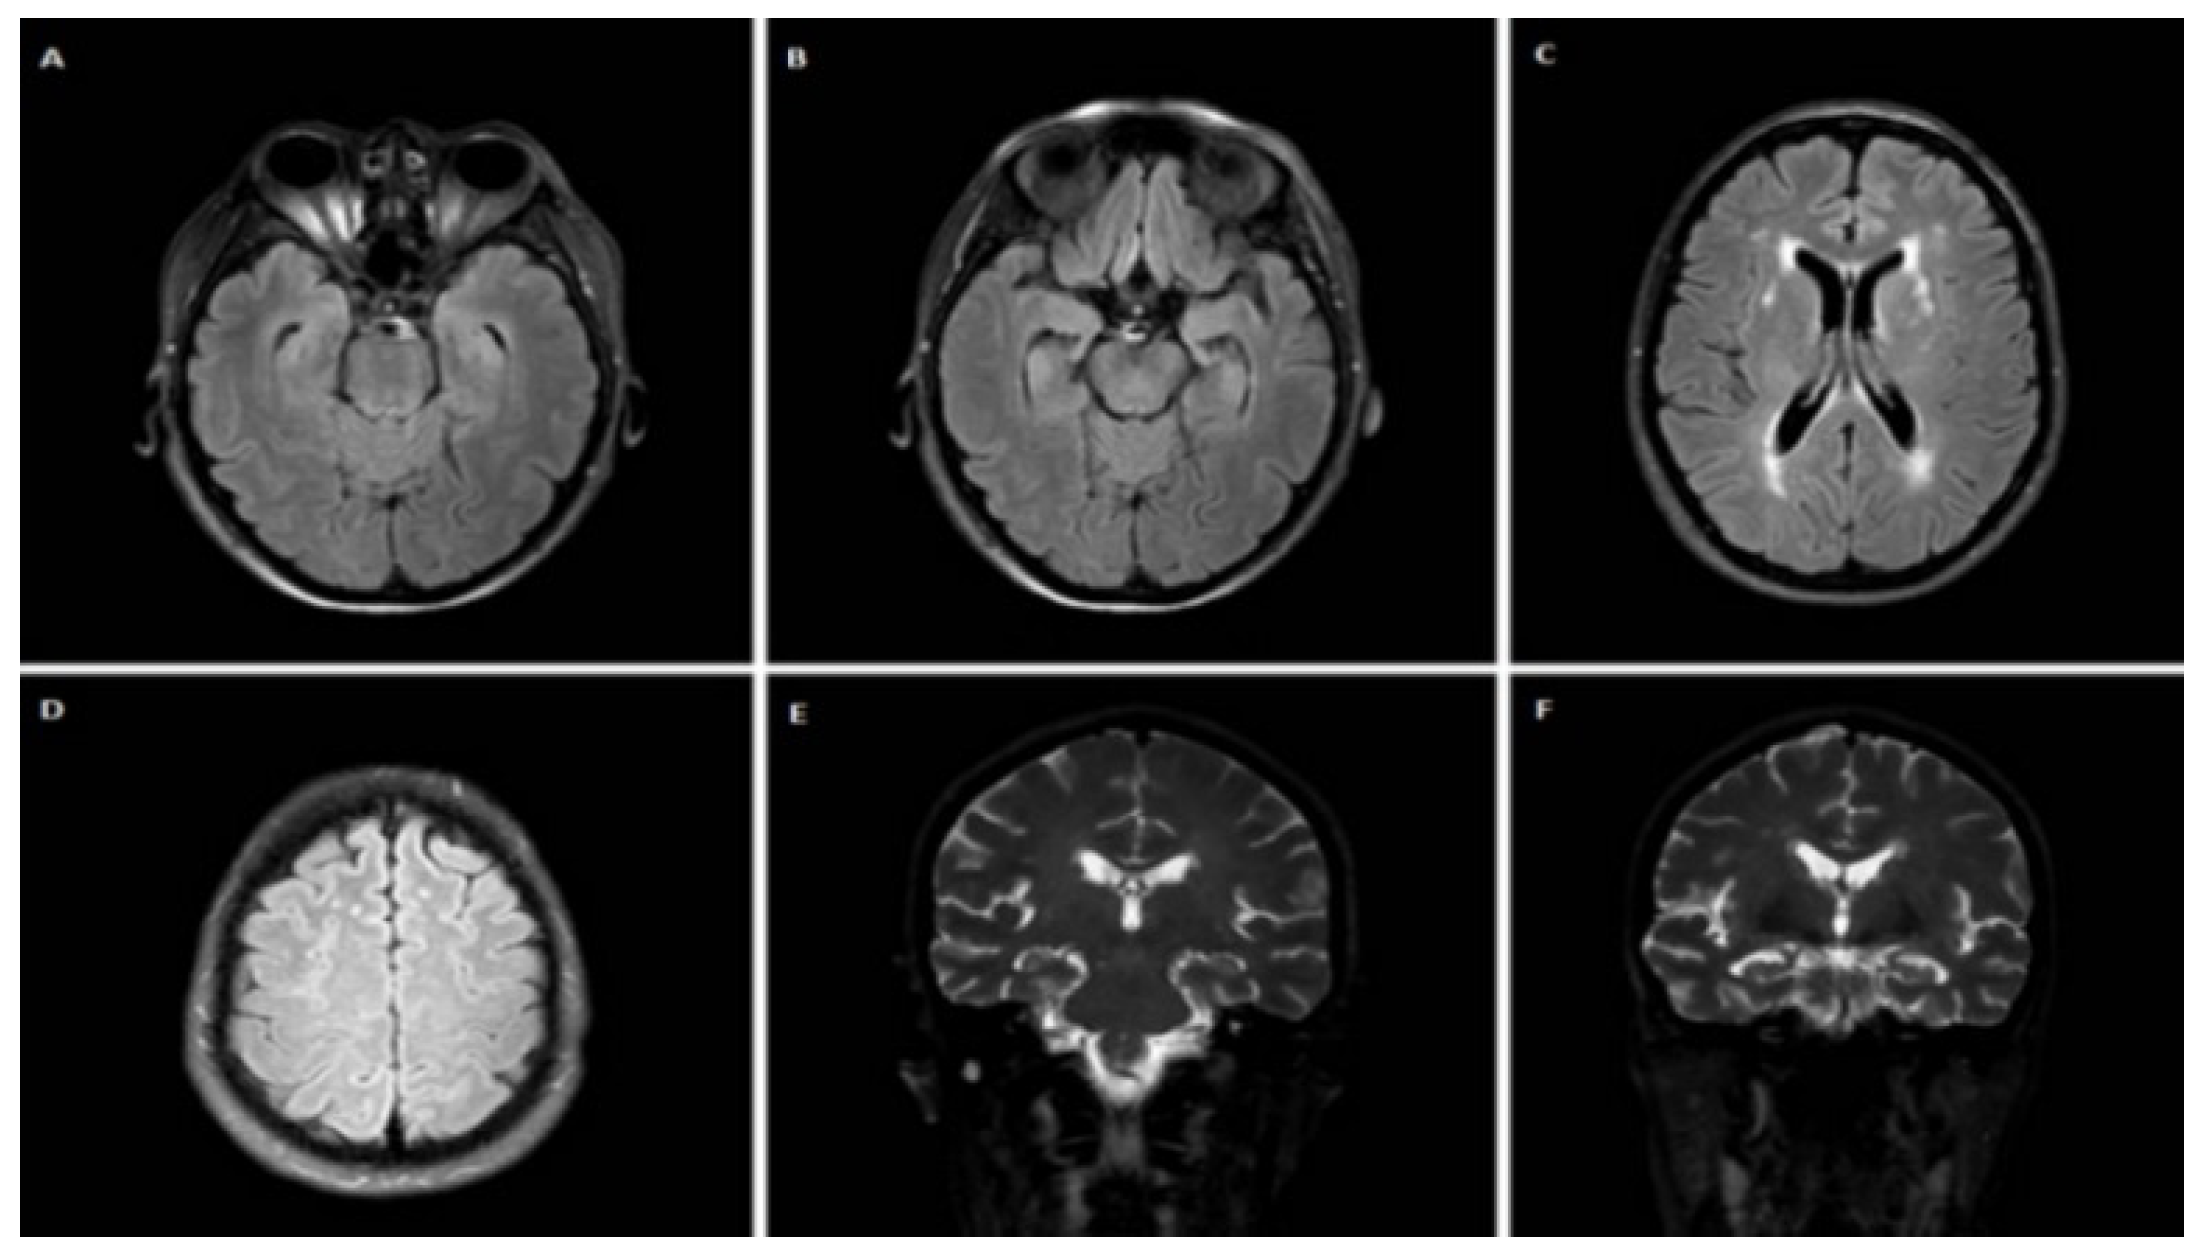

3.1.4. Case 4